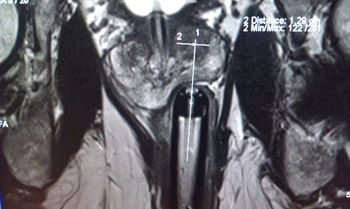

MRI Guided Focal Laser Ablation for Prostate CancerPublished: October 18th 2012 | Updated: